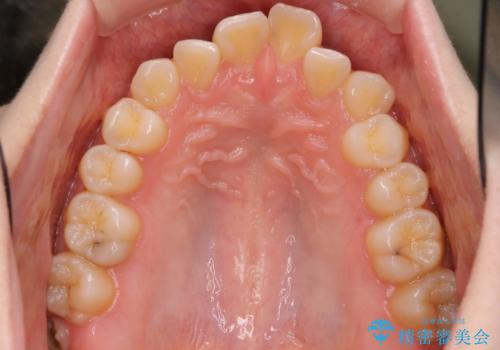

インビザラインによるガタつきの矯正治療 シンプル・短期間

- 非抜歯、IPR+拡大によるマウスピース矯正を計画した。

一見前歯のガタつきだけのように見えても、そのガタつきの根本的な原因が奥歯の位置であったりすると、マウスピースの枚数がそれなりに多くなり、治療に時間がかかることもあります。